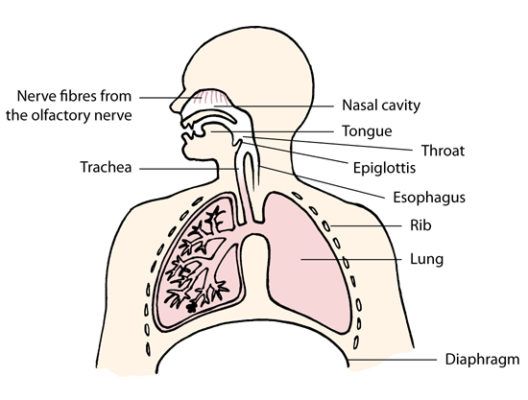

Your incredible nose

Use your nose! When air enters your nose, the many small hairs in your nose...

The Human Lungs

Breathing and flow in upper airways Let us take a closer look at the movement...